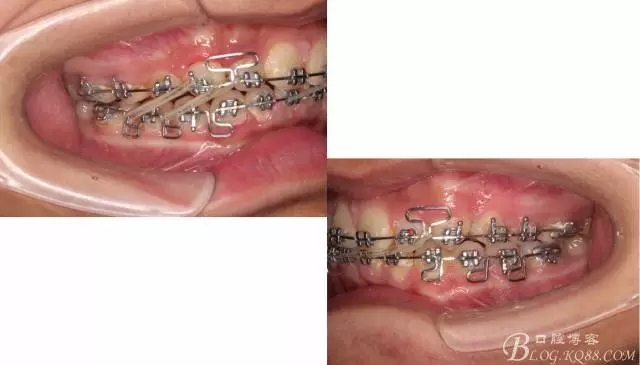

下頜配合多曲方絲,三角牽引,調(diào)整咬合。

中線不齊,咋辦?繼續(xù)哄哄患者配合,2牽+斜牽。

努力沒有白費,中線基本對齊!